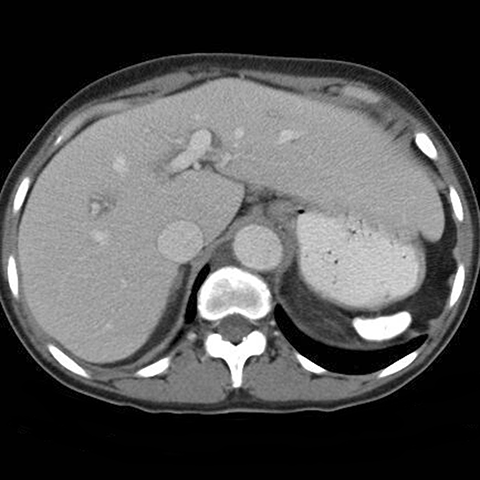

35-year-old male with sickle cell anemia presents with abdominal pain .